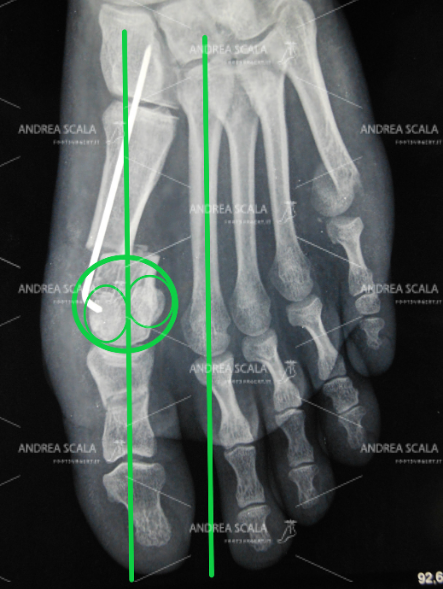

L’intervento del dott. Andrea Scala corregge tutte le deformità dell’alluce e del 1° metatarso. I pazienti operati possono autonomamente osservare le RXgrafie dopo l’intervento e capire da soli se l’intervento è stato correttamente eseguito. Si devono osservare le tre importanti correzioni:

– correzione dell’angolo tra il primo metatarso e alluce;

– correzione dello spostamento mediale del primo metatarso (angolo intermetatarsale);

– correzione della posizione dei sesamoidi.

La foto mostra il risultato dell’intervento ottenuto con la tecnica mini-invasiva del dott. Andrea Scala.

La RXgrafia post-operatoria spiega bene i motivi del corretto risultato ottenuto con la tecnica mini-invasiva del dott. Andrea Scala. Tutte le deformità sono state corrette. La testa del 1° metatarso (“cipolla”) è stata tagliata e spostata. L’alluce è stato allineato. I due metatarsi sono paralleli e non più divaricati I sesamoidi sono stati riposizionati sotto la testa del 1° metatarsale. Con questa metodica c’è l’assicurazione che l’alluce valgo non può tornare.